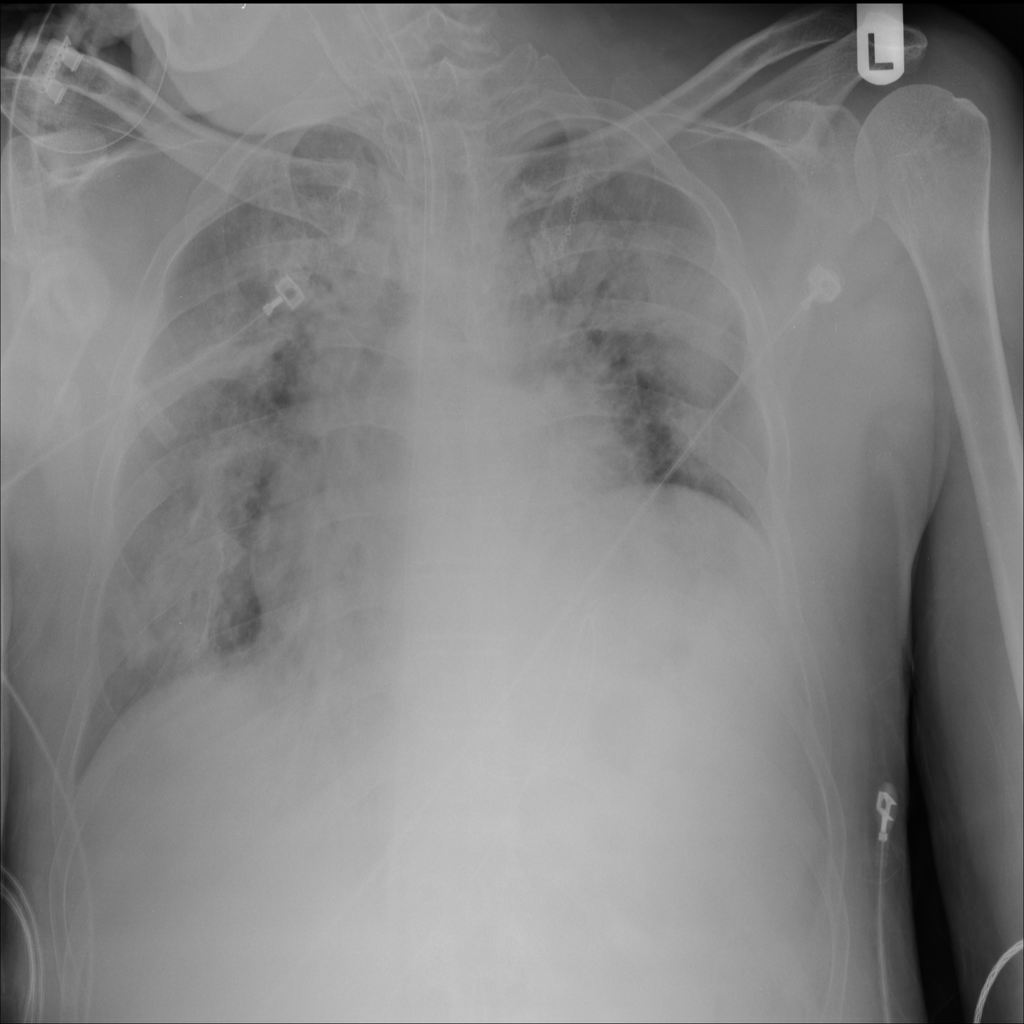

PAT-0B33 · IMG-013Pneumothorax

PAT-0B33 · IMG-013

AP